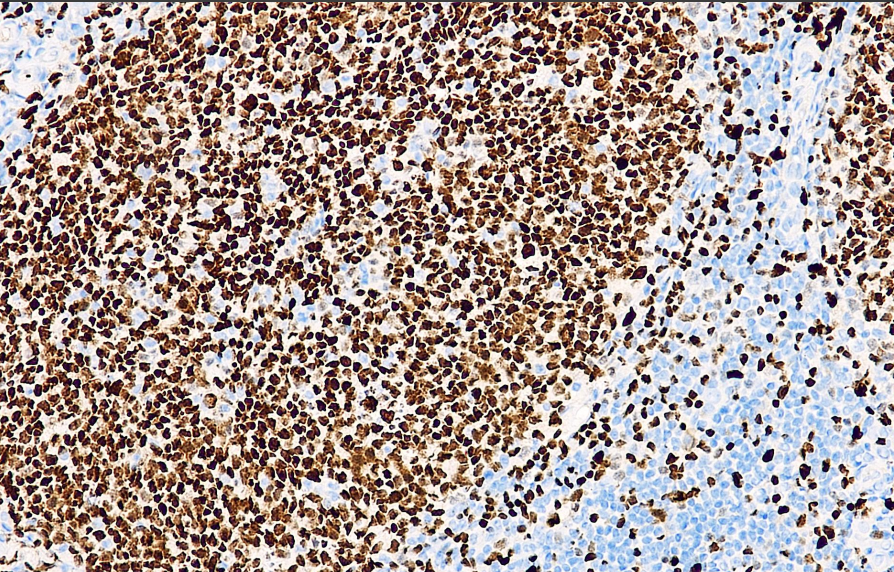

阳性对照: 扁桃体

PU.1作为一个转录因子,属于Ets蛋白家族,在正常B细胞的发育过程中发挥重要作用。在骨髓细胞系及B细胞中表达,浆细胞不表达。 PU.1在B细胞的早期分化过程是必不可少的,若缺乏会使B细胞发育停滞在早前期。 PU.1在生发中心和套区B细胞中表达,同样在各种淋巴瘤中表达,其中包括:慢性B淋巴细胞白血病、套细胞淋巴瘤、滤泡性淋巴瘤、边缘区淋巴瘤、弥漫性大细胞淋巴瘤、弥漫性大B细胞淋巴瘤、结节性淋巴细胞霍奇金淋巴瘤。Torlakovic等人的研究表明在滤泡性淋巴瘤中生发中心抗原(包括PU.1)的高表达与总生存期和进展生存期有着可量化的正相关联系。

PU.1抗体试剂可与PU.1分子抗原特异性结合,含PU.1抗体试剂的免疫组化试剂盒适用于急性髓系白血病/AML、淋巴瘤等的辅助诊断。